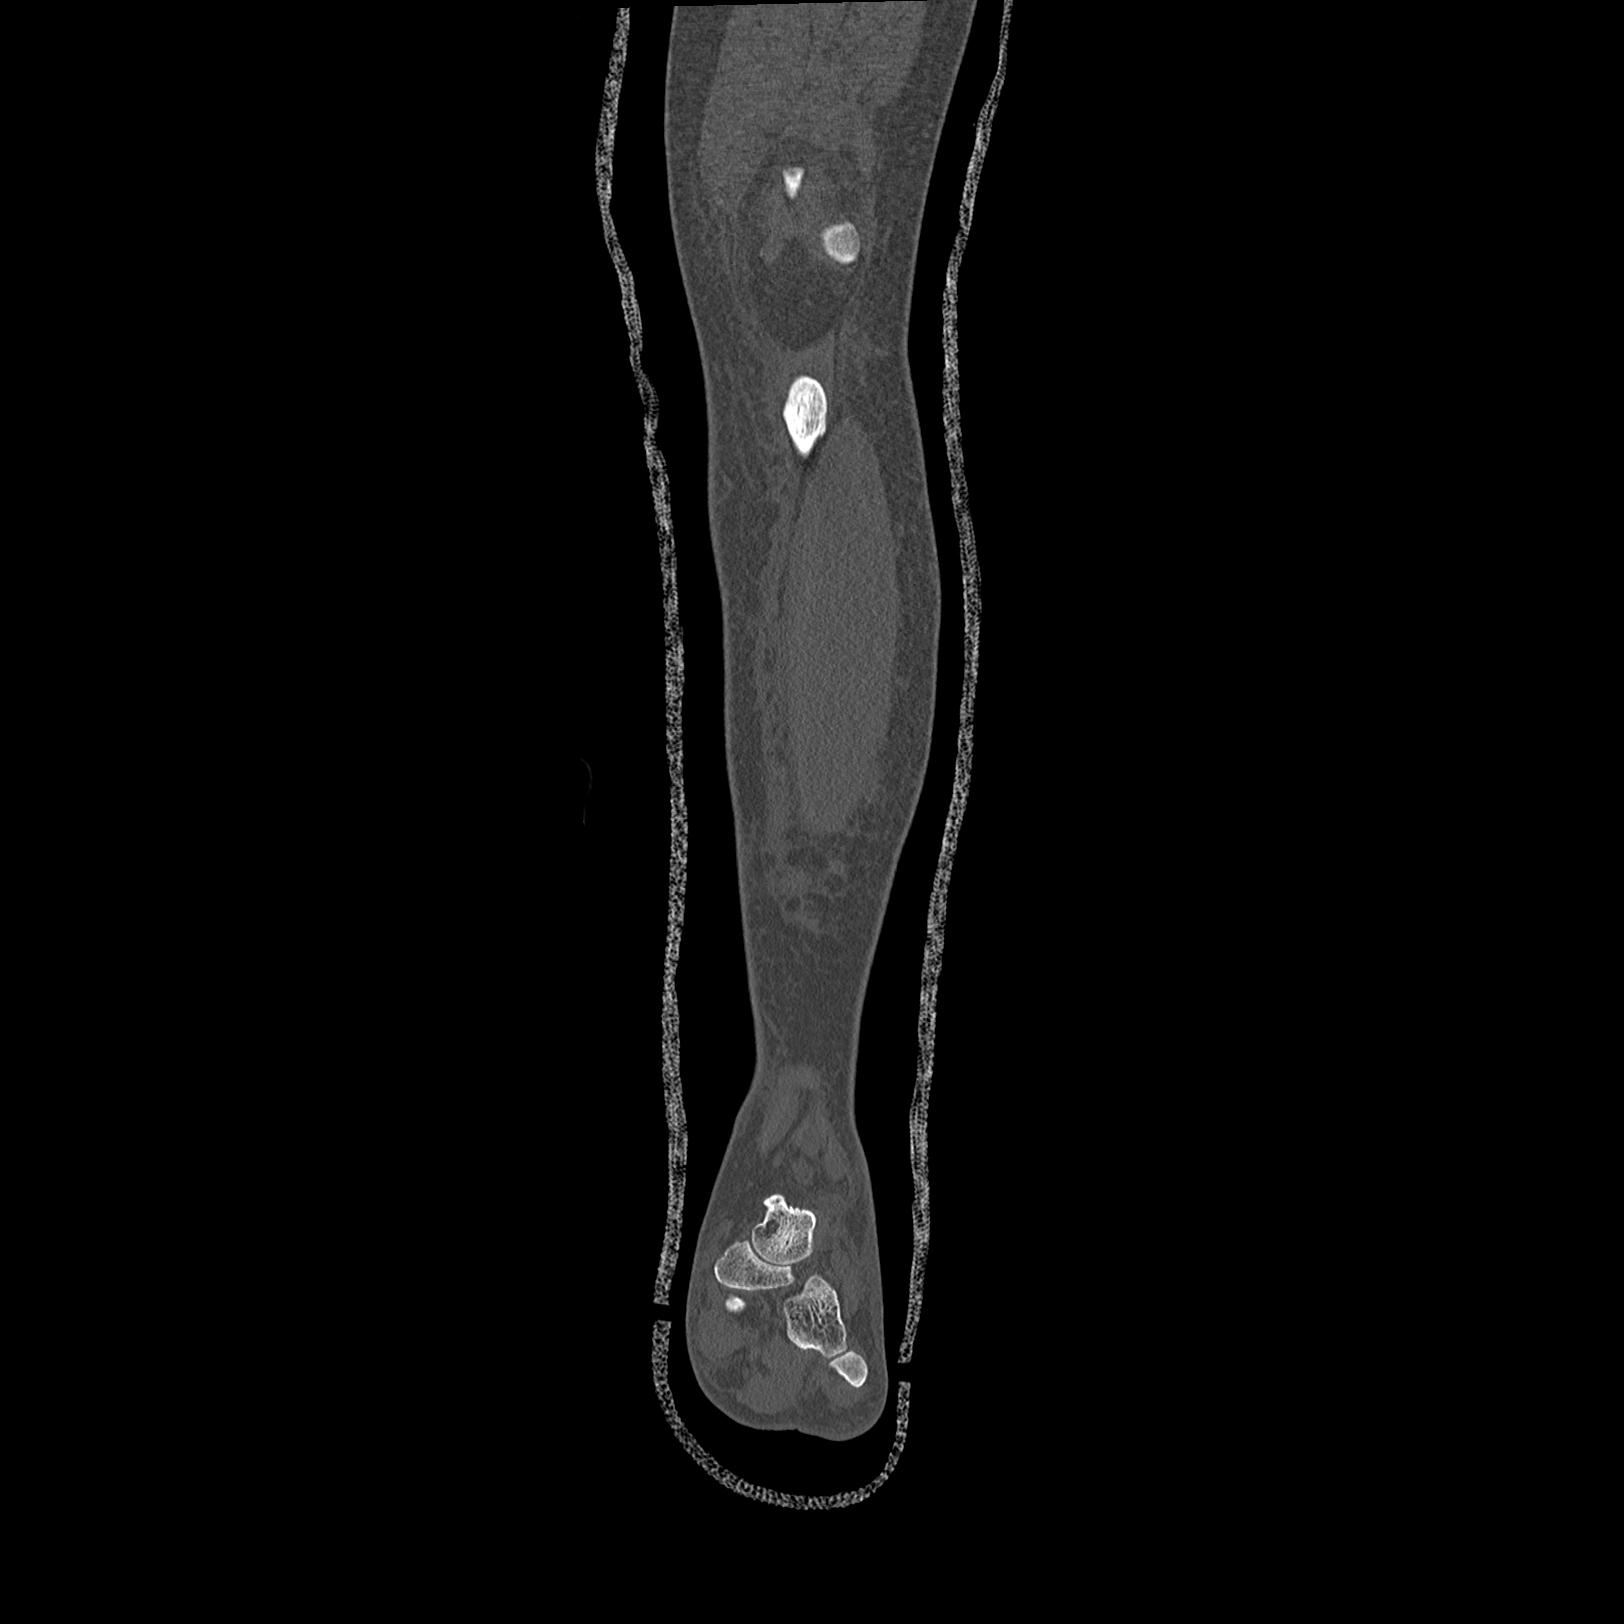

102803 1/12(キウスなし) 1/27 左下腿 4R 30歳女性 左脛骨軸内釘